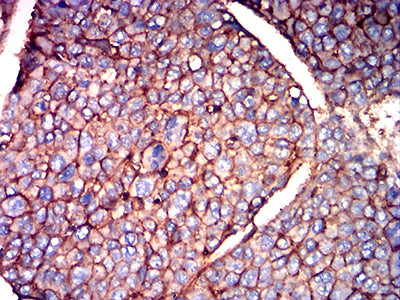

分类: 科研抗体货号: 31937别名: BSG; OK; 5F7; TCSF; EMMPRIN应用: IHC,FCM反应种属: Human